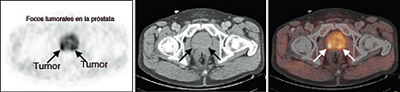

El estudio de los huesos mediante gammagrafía ósea debe ser efectuado si hay sospecha de lesiones óseas y/o el PSA es superior a 10 ng/ml. En ocasiones se realiza un PET-TC con colina para evaluar la presencia de metástasis.

RMN endorectal. Es una técnica de imagen que utiliza ondas magnéticas en lugar de rayos-X. La energía de las ondas magnéticas es absorbida por el organismo y después liberada dando las imágenes más detalladas que hoy en día podemos obtener de la próstata. La calidad de las imágenes, asociada en ocasiones con técnicas de espectroscopia o de inyección de contraste paramagnético es tan elevada que permite observar la zona de HBP y, si hay tumor, diferenciar entre un tumor en estadio T2 y un T3 con una especificidad del 95%. También permite detectar la presencia de ganglios linfáticos aumentados de tamaño, en la zona pelviana y es de gran ayuda para planificar las biopsias pues nos indica que áreas son sospechosas de albergar células cancerosas.